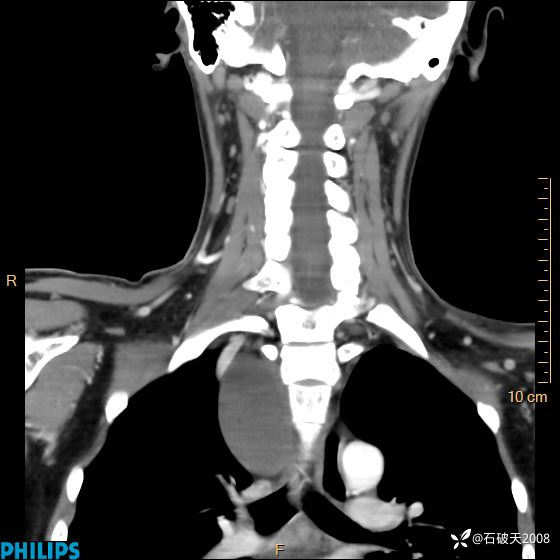

冠状位

静脉期